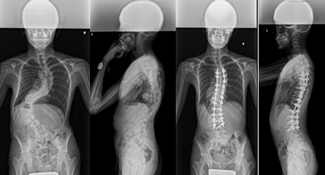

後方矯正固定術

せなかを切開してチタンなどで作られた椎弓根スクリューをせぼねに挿入して、ロッドと呼ばれる金属のバーで固定して、せぼねの矯正と固定を行います。術後に手術部の安静を保つために装具を3-6ヶ月程度着用します。